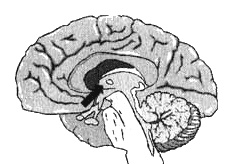

Глубокая лимбическая система

Вид сбоку